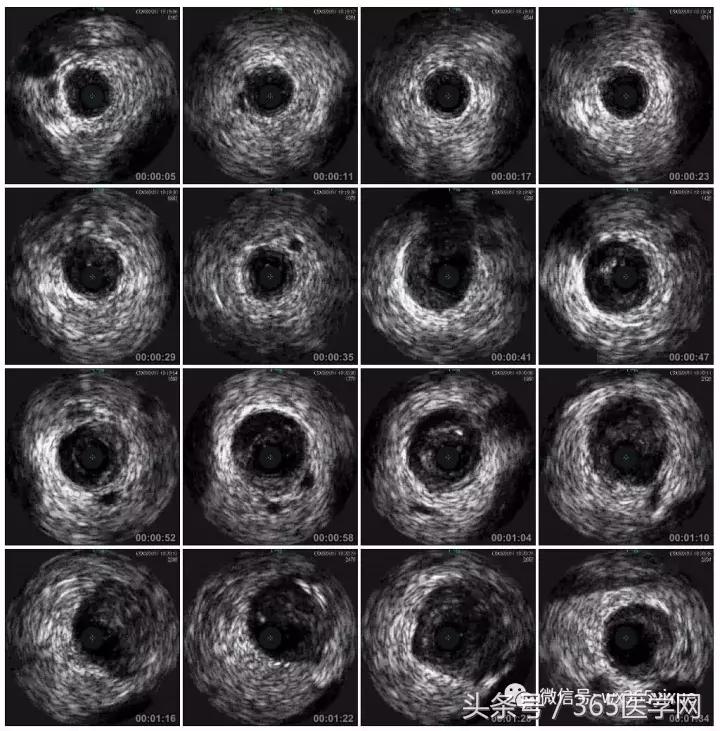

首先:IVUS指导下干预LAD

4.0mm*13mm药物支架

RCA闭塞段球囊扩张后IVUS

支架术后IVUS